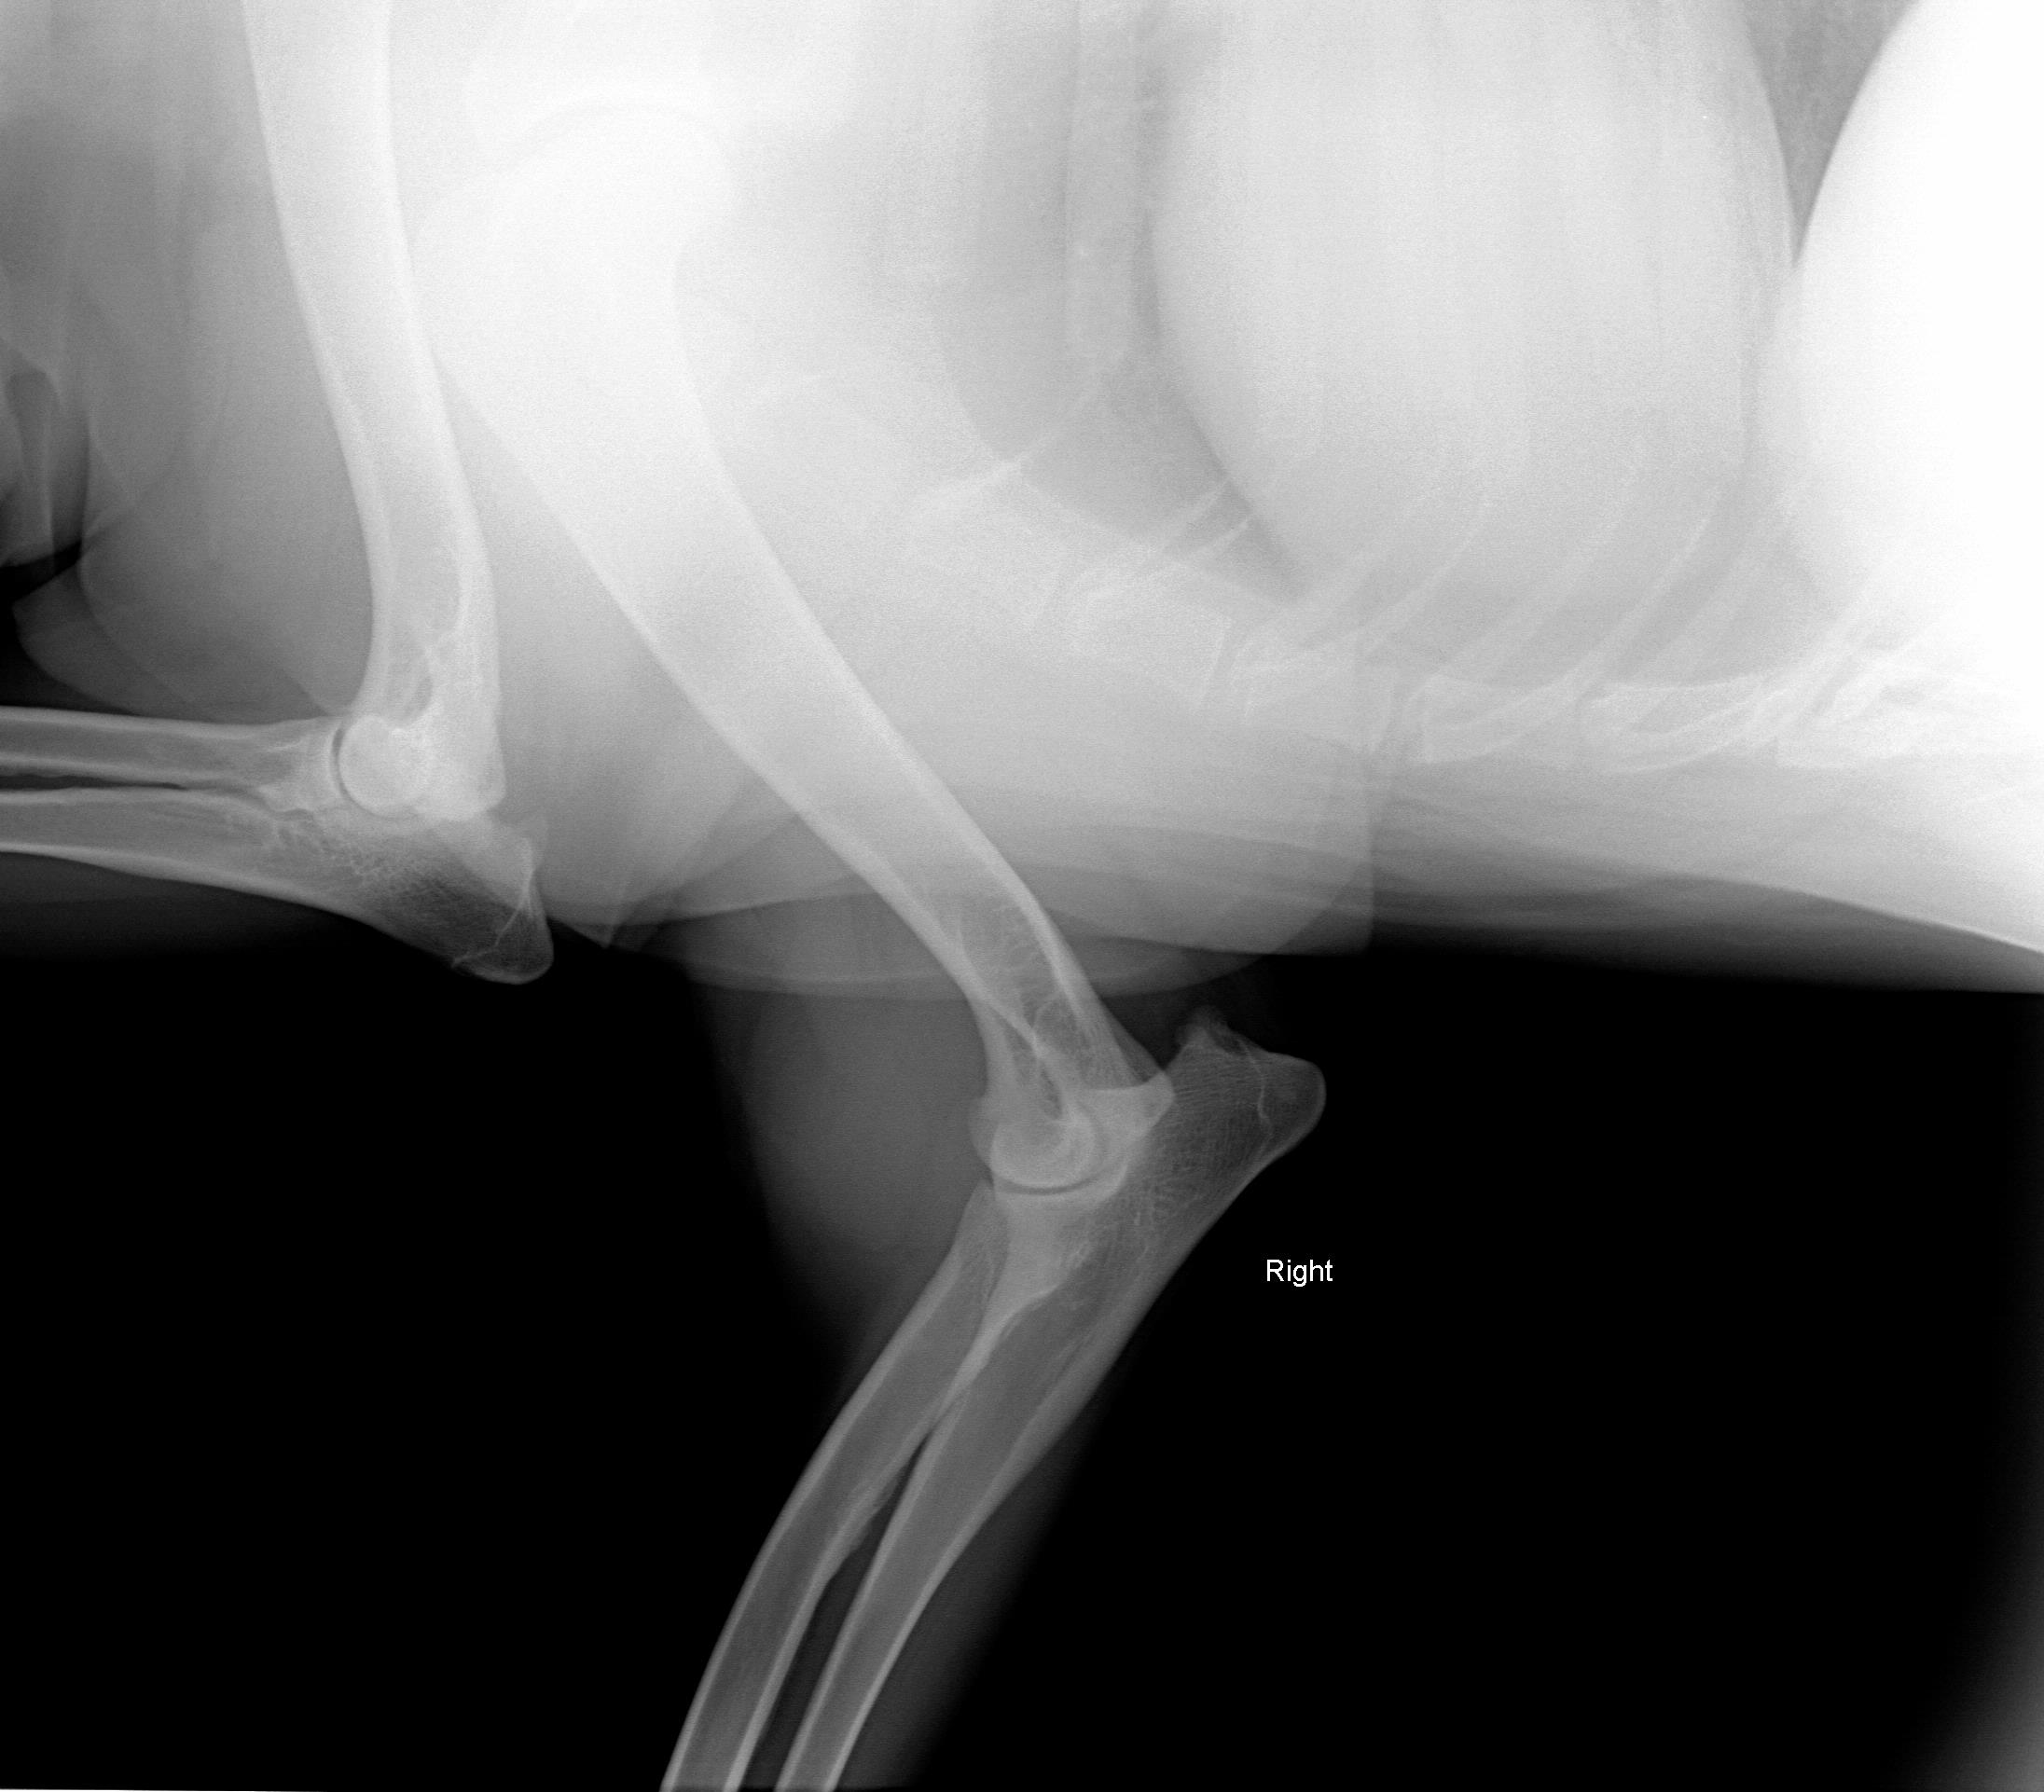

August 1, 2008 - X-rays taken at AMVC in Audubon, IA by Dr. Kristin Longfellow. She was not sedated for the x-rays. She was in slight discomfort in the area of the elbow if pressure was applied, at times seeing her trying to put weight on her toes, she was not in distress, but stiff and sore. We increased her metacam up to her weight limit.

August 4, 2008, Zoey was miserable, reluctance to go down two steps; favoring her front leg; licking it; swelling around elbow; very limited movement, etc. The swelling on the right elbow is not warm, nor cold to touch (unchanged). The swelling is hard/solid. Zoey was sleeping on her blanket (orthoped bed) on the floor without attempting to get on the bed with us at night. Zoey's eyes said she was miserable even though she was trying not to show it. The right leg is clearly marked on the xrays. She was conscious and not sedated for the xrays.

Zoey seen August 1, 2008 by Dr. Kristin Longfellow

due to limping and swelling of the front right forearm/elbow/shoulder area.

X-rays below.

On July 3, 2008, after Zoey finished her pig ear she was chasing her tail and caught the corner of the wall and never recovered from her injuries.The xray was taken 2/13/09

The following xrays were taken August 2008.